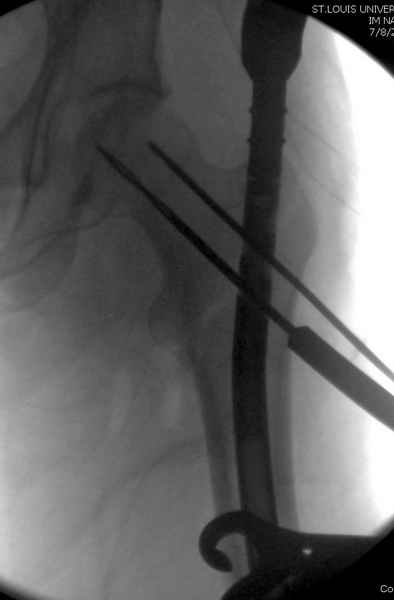

Как раз недавно у меня был примерный случай: больному 36 лет, поступил ночью, травма в результате мотоциклетной аварии, кроме чрезвертельного и спирального перелома левого бедра имеется переломы костей предплечья с этой же стороны. Скелетное вытяжение, а на следующий день больной про оперирован на ортопедическом столе с дистракцией. Чтобы не расколоть чрезвертельный перелом провели временную спицу ближе к переднему кортексу, из малого разреза костодержатель для репозиции, а фиксацию провели антиградным штифтом. Этапы операции на снимках.

Джолдас Кульджанов